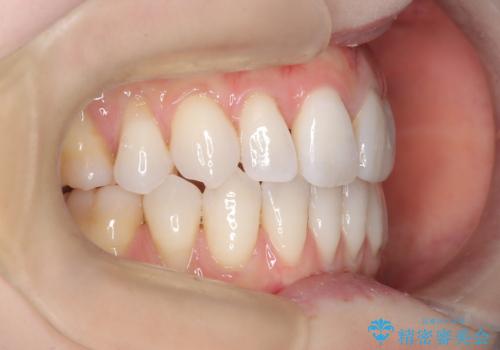

ハーフリンガル矯正|上下4本の抜歯で叢生を改善し、美しい歯並びへ

- 患者様は、歯並びの乱れ(叢生)を整えたいが、前歯の突出感は気にならないとのことで来院されました。診察の結果、全体的な歯列のスペース不足により抜歯が必要と判断。しかし、前歯を大きく下げる必要はなかったため、小臼歯の中でも5番(第二小臼歯)を抜歯する治療計画を立てました。装置は、上顎が舌側(リンガル)、下顎が表側(審美ワイヤー)のハーフリンガル矯正を採用し、目立ちにくさと効率的な歯の移動を両立しました。

抜歯によって歯を並べるためのスペースを確保。その後、ハーフリンガル矯正を用いて、上顎は舌側から、下顎は目立ちにくいワイヤーで歯を誘導し、歯列全体を整えました。治療期間を通じて、噛み合わせのバランスも改善し、機能的にも審美的にも理想的な仕上がりとなりました。患者様からは「目立たずに矯正でき、きれいな歯並びになって嬉しい」とご満足いただきました。